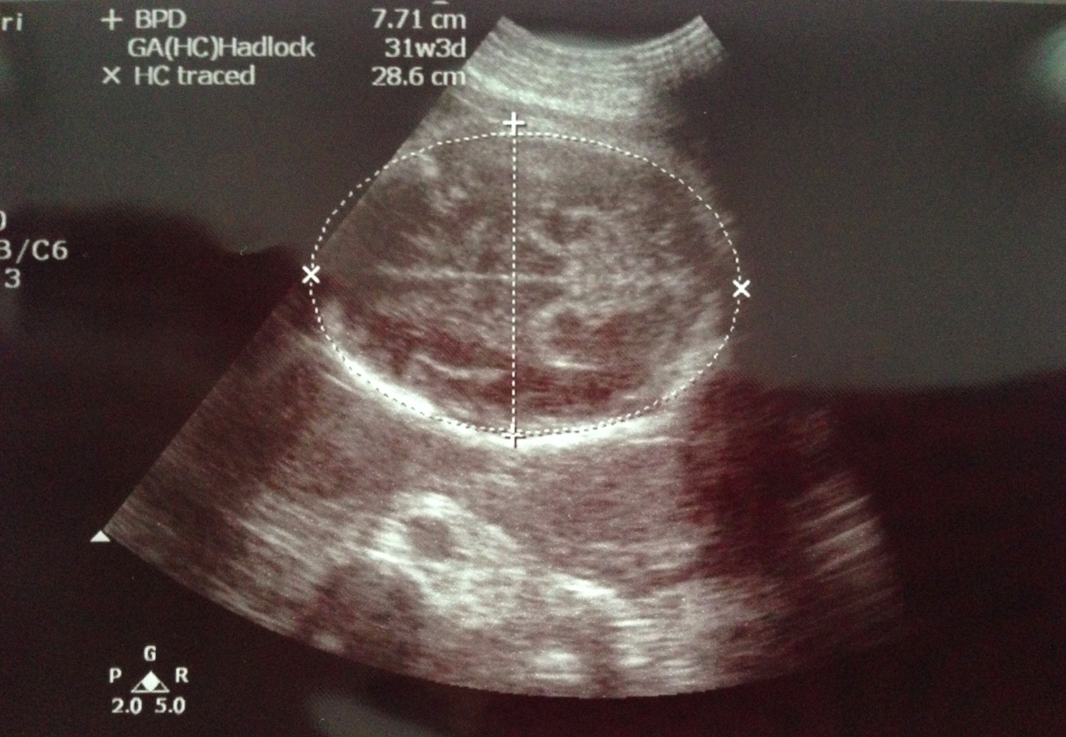

指定動作﹗頭仔先~而家頭仔直徑有7.71cm,超聲波機計算嘅週數係31w3d,S醫生話而家嘅週數嚟講正負兩星期都屬於正常~ 閱讀全文